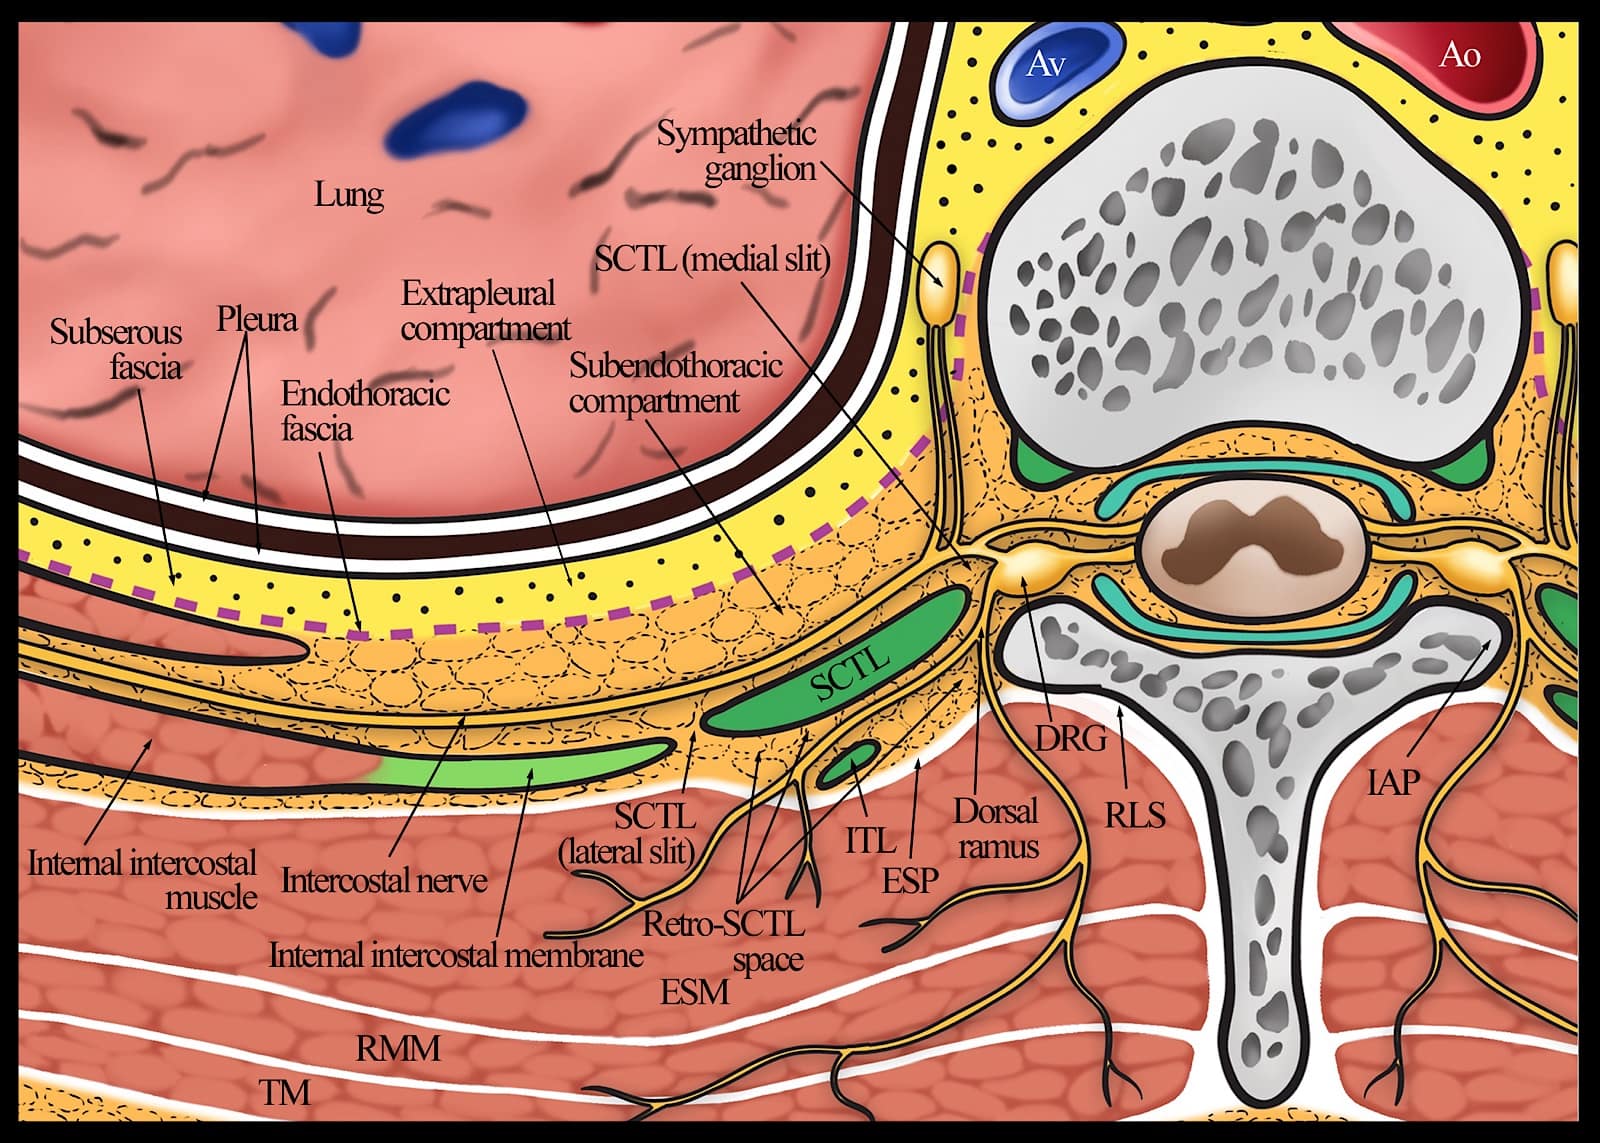

The TPVS is a wedge-shaped space located on either side of the thoracic vertebral column behind the parietal pleura (Figure 1).1 It is wider on the left than on the right, and the base is formed by the vertebral body, intervertebral disc, and intervertebral foramen (Figure 1).1 The parietal pleura forms the anterolateral boundary (Figures 1-2), while the superior costotransverse ligament (SCTL), which extends from the lower border of the transverse process (TP) above to the upper border of the TP below, forms the posterior boundary (Figures 2-3).1 The inter-transverse ligament, thinner than the SCTL, also extends between adjacent transverse processes (Figure 3). The SCTL is continuous laterally with the internal intercostal membrane (IICM), the medial extension of the internal intercostal muscle (Figure 3). The apex of the TPVS is continuous with the posterior intercostal space (PICS) lateral to the tip of the TP (Figures 1 and 3).1 While the SCTL forms the posterior boundary of the TPVS, it is not a water-tight barrier. Fenestrations and gaps have been identified within the architecture of the SCTL,27-29 and an injection behind the SCTL or into the intertransverse tissue complex (ITTC) can make its way to the paravertebral space.30,31 The ITTC comprises the SCTL, intertransverse ligament, posterior costotransverse ligament (if present), intertransverse and levator costarum muscles, and fatty connective tissue.32

Figure 1. Transverse anatomy of the thoracic paravertebral region.

Reproduced with permission from the Department of Anesthesia and Intensive Care, The Chinese University of Hong Kong, Faculty of Medicine, www.aic.cuhk.edu.hk/usgraweb.

Between the parietal pleura and the SCTL lies the fibroelastic endothoracic fascia (Figure 1-2), which is the deep fascia of the thorax and lines the internal aspect of the thoracic cage (Figure 4).33,34 At the TPVS, the endothoracic fascia is loosely attached to the ribs (Figure 2) and/or the TP and fuses medially with the periosteum of the vertebral body (Figure 1).1 The subserous fascia, a layer of loose connective tissue, lies between the parietal pleura and the endothoracic fascia (Figure 1).1 The endothoracic fascia divides the TPVS into the anterior extrapleural paravertebral compartment and the posterior subendothoracic paravertebral compartment (Figure 1-2).1 The TPVS contains fatty tissue within which lie the intercostal (spinal) nerve, dorsal ramus, intercostal vessels, rami communicantes, and the sympathetic chain (Figure 1-2).1 The spinal nerve in the TPVS divides into multiple small bundles without a fascial sheath, making them vulnerable to injected LA.1 The intercostal nerve and vessels are located behind the endothoracic fascia, while the sympathetic trunk is located anterior to it (Figure 2-4).1

The TPVS is continuous with the contiguous space above and below,34 the epidural space medially via the intervertebral foramen,35 the intercostal space laterally; and the contralateral TPVS via the epidural and prevertebral space (Figure 1-3.).34 Communication with the contiguous paravertebral spaces above and below occurs not only via the paravertebral space,34 but also via the costotransverse space.36-38 The anatomy of the TPVS has recently been redefined with the characterization of the SCTL and identification of the “retro-SCTL space” (Figures 5 and 6), using three-dimensional micro-CT imaging of paravertebral tissue specimens in cadavers.36 Contrary to previous understanding,1 the SCTL forms an incomplete posterior wall of the TPVS with the lateral and medial slits (see Figures 3 and 5).29,39 The former lies laterally between the IICM and the SCTL while the latter lies medially between the SCTL and the vertebral body (Figures 3 and 5).29,39 The costotransverse space, located between the neck of the rib and the transverse process, is filled with fat and loose connective tissue and is visible as a distinct anatomical space in micro-CT images.36 The retro-SCTL space36 also filled with fat, and connective tissue communicates with the erector spinae and retrolaminar planes posteriorly, TPVS anteriorly via the lateral and medial slits in the SCTL,29 intervertebral canal and epidural space medially,37 the intercostal space laterally via the lateral slit in the SCTL (Figures 5 and 6), and with the contiguous TPVS and retro-SCTL space above and below via the costotransverse space.36,37 The location of the costotransverse foramen within this redefined paravertebral anatomy is unclear. However, it might represent the medial end of the retro-SCTL space as depicted in Figures 5 and 6,29,37 given its proximity to the base of the transverse process and inferior articular process (IAP).

Figure 5. Transverse anatomy of the thoracic paravertebral region showing the anatomic relationship of the thoracic paravertebral space to the retro-SCTL space and neuraxis. Note the medial and lateral slits in the SCTL and the position (not to scale) of the ITL. Also note that both the ventral and dorsal rami of the spinal nerve are initially located within the medial aspect of the retro-SCTL space before the ventral ramus enters the thoracic paravertebral space through the medial slit in the SCTL, and the dorsal rami travels posteriorly toward the paraspinal muscles.

Ao = descending aorta, Av = azygos vein, DRG = dorsal root ganglion, ESP = erector spinae plane, ESM = erector spinae muscle, IAP = inferior articular process, ITL = intertransverse ligament, RLS = retrolaminar space, RMM = rhomboid major muscle, SCTL = superior costotransverse ligament, TM = trapezius muscle